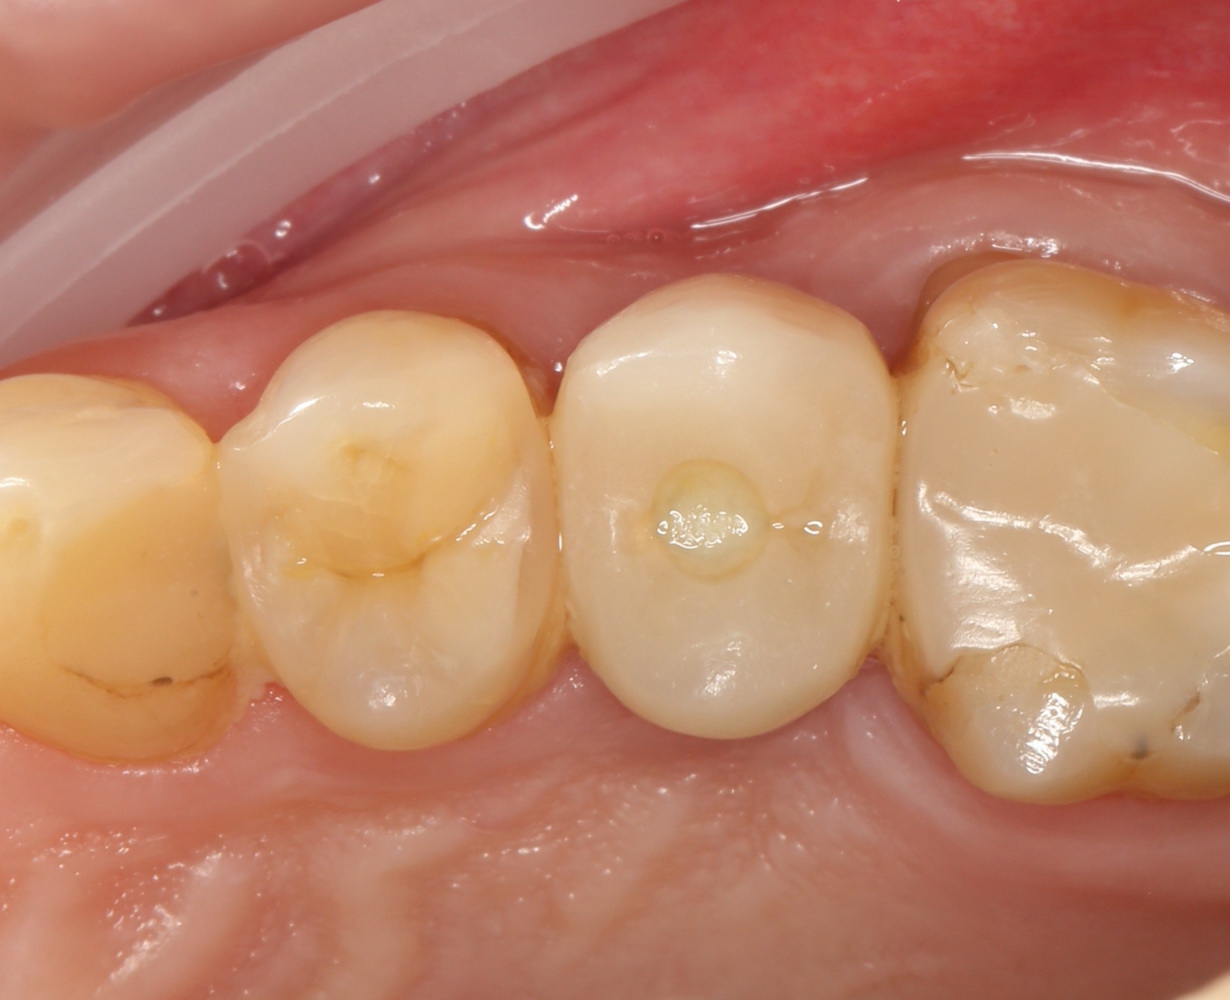

А еще через 2,5-3 месяца можно приступать к протезированию. Мой коллега Макаров Артур сделал временную коронку:

Временная коронка изготавливается из обычной пластмассы, поэтому с цветом особо не заморачиваются. Гораздо важнее состояние десны вокруг коронки (имхо, почти идеально) и ее функционал. Коллега-пациент говорит, что уже забыл, что этот зуб когда-то удаляли.